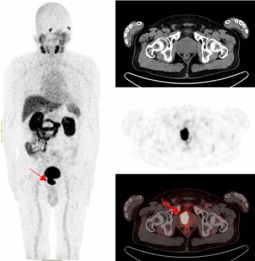

一名75的岁男性患者自2019年确诊前列腺癌后,先后接受过两次内分泌治疗及前列腺癌根治术的综合治疗。在术后两年的复查中发现血PSA持续升高,CT检查和全身骨显像检查均未发现明显异常,医生建议随诊,患者来到江南大学附属医院要求进一步检查。经核医学科68Ga-PSMA PET/CT检查后结果显示,双侧肩胛骨、左侧第9后肋、第2腰椎及纵隔淋巴结均已存在癌症转移。